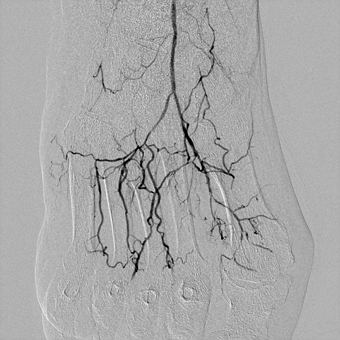

— У пациентов с синдромом диабетической стопы, к сожалению, чаще выполняется ампутация конечности, чем попытка восстановления кровотока в пораженной конечности. Хотя на сегодняшний день возможности сосудистой и эндоваскулярной хирургии позволяют если не сохранить конечность целиком, то хотя бы сберечь ее опорную функцию, тем самым сохранив пациенту мобильность, а значит и высокое качество жизни. Эта пациентка поступила к нам с сухой гангреной без инфицирования 1, 2, 3 пальцев правой стопы 2А степени по классификаци Техасского университета. Была предпринята попытка эндоваскулярной реконструкции пораженных артерий бедра и голени, критическое сужение или окклюзия которых и приводит к синдрому диабетической стопы и необходимости ампутации. Нами была выполнена реканализация подколенной, передней большеберцовой артерии и малоберцовой артерии правой ноги. Полностью пройти подошвенную дугу и заднюю большеберцовую артерию не удалось, но, несмотря на это, полностью был восстановлен кровоток в стопе и пальцах.

![]() Окклюзия артерий стопы |

![]() Артерии стопы заполняются полностью |

В дальнейшем пациентка была переведена в отделение гнойной хирургии ГБУЗ «ГКБ № 67 им. Л. А. Ворохобова ДЗМ» для оперативного лечения (удаления некротизированных тканей пальцев). Благодаря восстановлению кровотока в артериях нижней конечности удалось сохранить стопу и опорную функцию ноги.